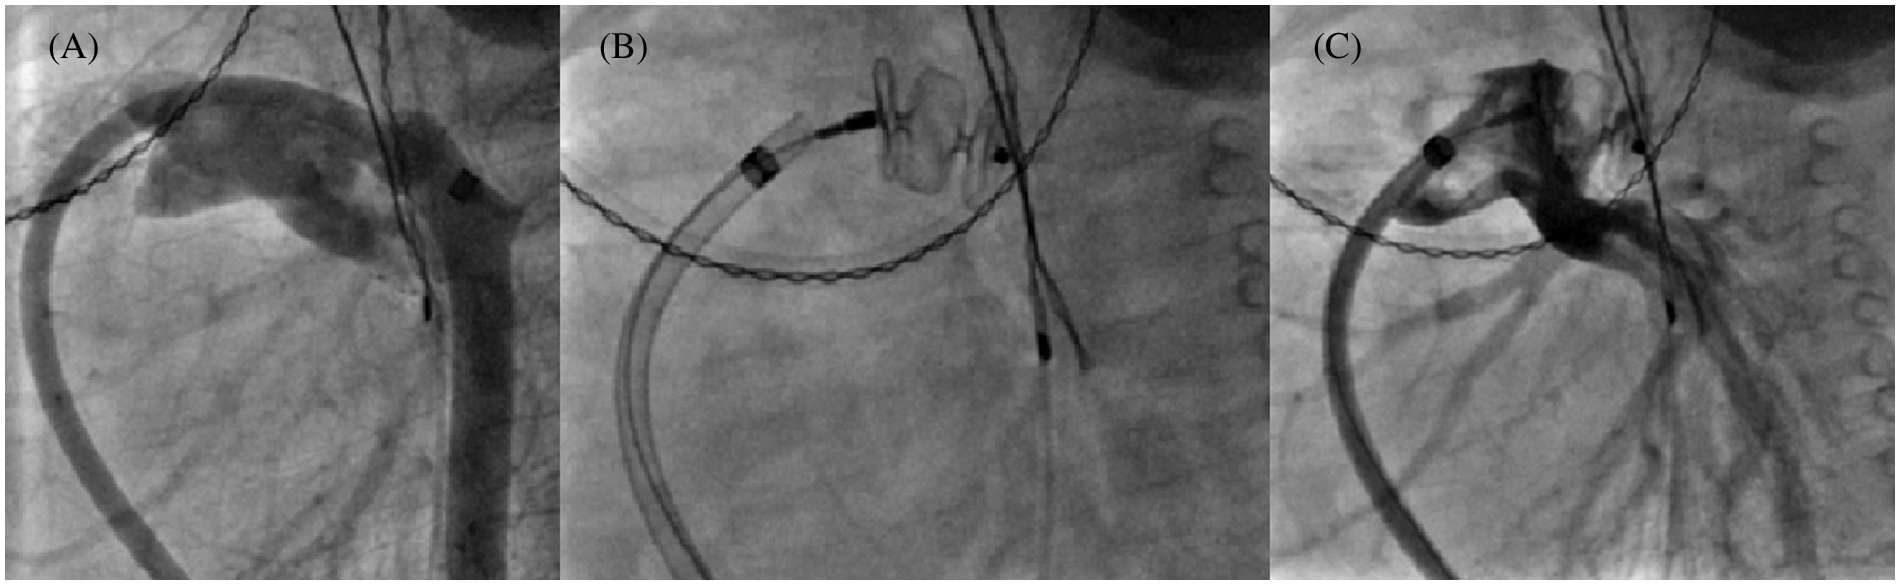

Over a 14 year-period, 125 children under 10 years (57.6% female, mean age: 2.8 ± 3.1 years, mean weight 13.9 ± 13.7 kg) underwent 136 procedures using either AVP II and/or AVP IV for the percutaneous treatment of 147 different lesions. Overall, 169 plugs (60 AVP II and 109 AVP IV) were successfully implanted out of the 171 initially engaged. As such, two procedures failed due to poor patient tolerance requiring withdrawal before release. The first procedure failure involved an infant who developed immediate left pulmonary artery (LPA) stenosis (Fig. 2) during closure of a large PDA (AVP II). The second failure concerned another patient in whom the obliteration (AVP IV) of a lobar sequestration collateral artery induced an immediate acute chest pain syndrome.

Figure 2: 10 mm AVP II implantation failure in a 6 kg infant. Multiple angiograms, lateral view. (A): 6.5 mm tubular PDA by venous approach with small aortic arch; (B): 10 mm AVP II positioning; (C): Left pulmonary artery stenosis which became rapidly severe